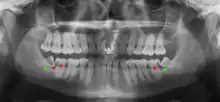

Wisdom teeth likely become impacted because of a mismatch between the size of the teeth and the size of the jaw. Impacted wisdom teeth are classified by their direction of impaction, their depth compared to the biting surface of adjacent teeth and the amount of the tooth's crown that extends through gum tissue or bone. Impacted wisdom teeth can also be classified by the presence or absence of symptoms and disease. Screening for the presence of wisdom teeth often begins in late adolescence when a partially developed tooth may become impacted. Screening commonly includes clinical examination as well as x-rays such as panoramic radiographs.

If the tooth cannot be assessed with clinical exam alone, the diagnosis is made using either a panoramic radiograph or cone-beam CT. Where unerupted wisdom teeth still have eruption potential several predictors are used to determine the chance of the teeth becoming impacted. The ratio of space between the tooth crown length and the amount of space available, the angle of the teeth compared to the other teeth are the two most commonly used predictors, with the space ratio being the most accurate. Despite the capacity for movement into early adulthood, the likelihood that the tooth will become impacted can be predicted when the ratio of space available to the length of the crown of the tooth is under 1.[5]:141

There is no standard to screen for wisdom teeth. It has been suggested, absent evidence to support routinely retaining or removing wisdom teeth, that evaluation with panoramic radiograph, starting between the ages of 16 and 25 be completed every 3 years. Once there is the possibility of the teeth developing disease, then a discussion about the operative risks versus long-term risk of retention with an oral and maxillofacial surgeon or other clinician trained to evaluate wisdom teeth is recommended. These recommendations are based on expert opinion level evidence.[19] Screening at a younger age may be required if the second molars (the "12-year molars") fail to erupt as ectopic positioning of the wisdom teeth can prevent their eruption. Radiographs can be avoided if the majority of the tooth is visible in the mouth.